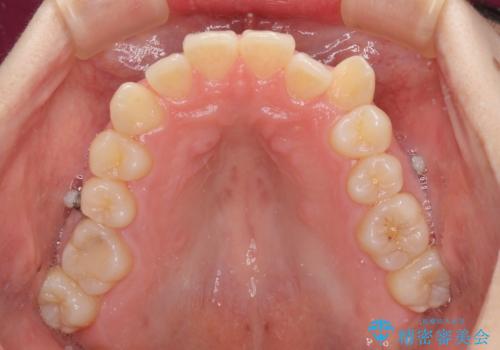

インビザラインによる矯正治療を希望されたため、上顎歯列の側方拡大奥歯の遠心移動のための補助装置を併用し、その後はインビザラインにて行うこととしました。

八重歯の動きが鈍く、治療期間は長期化しました。

癒着の疑いもありましたが、アンカースクリューを多用し、何とか改善することができました。